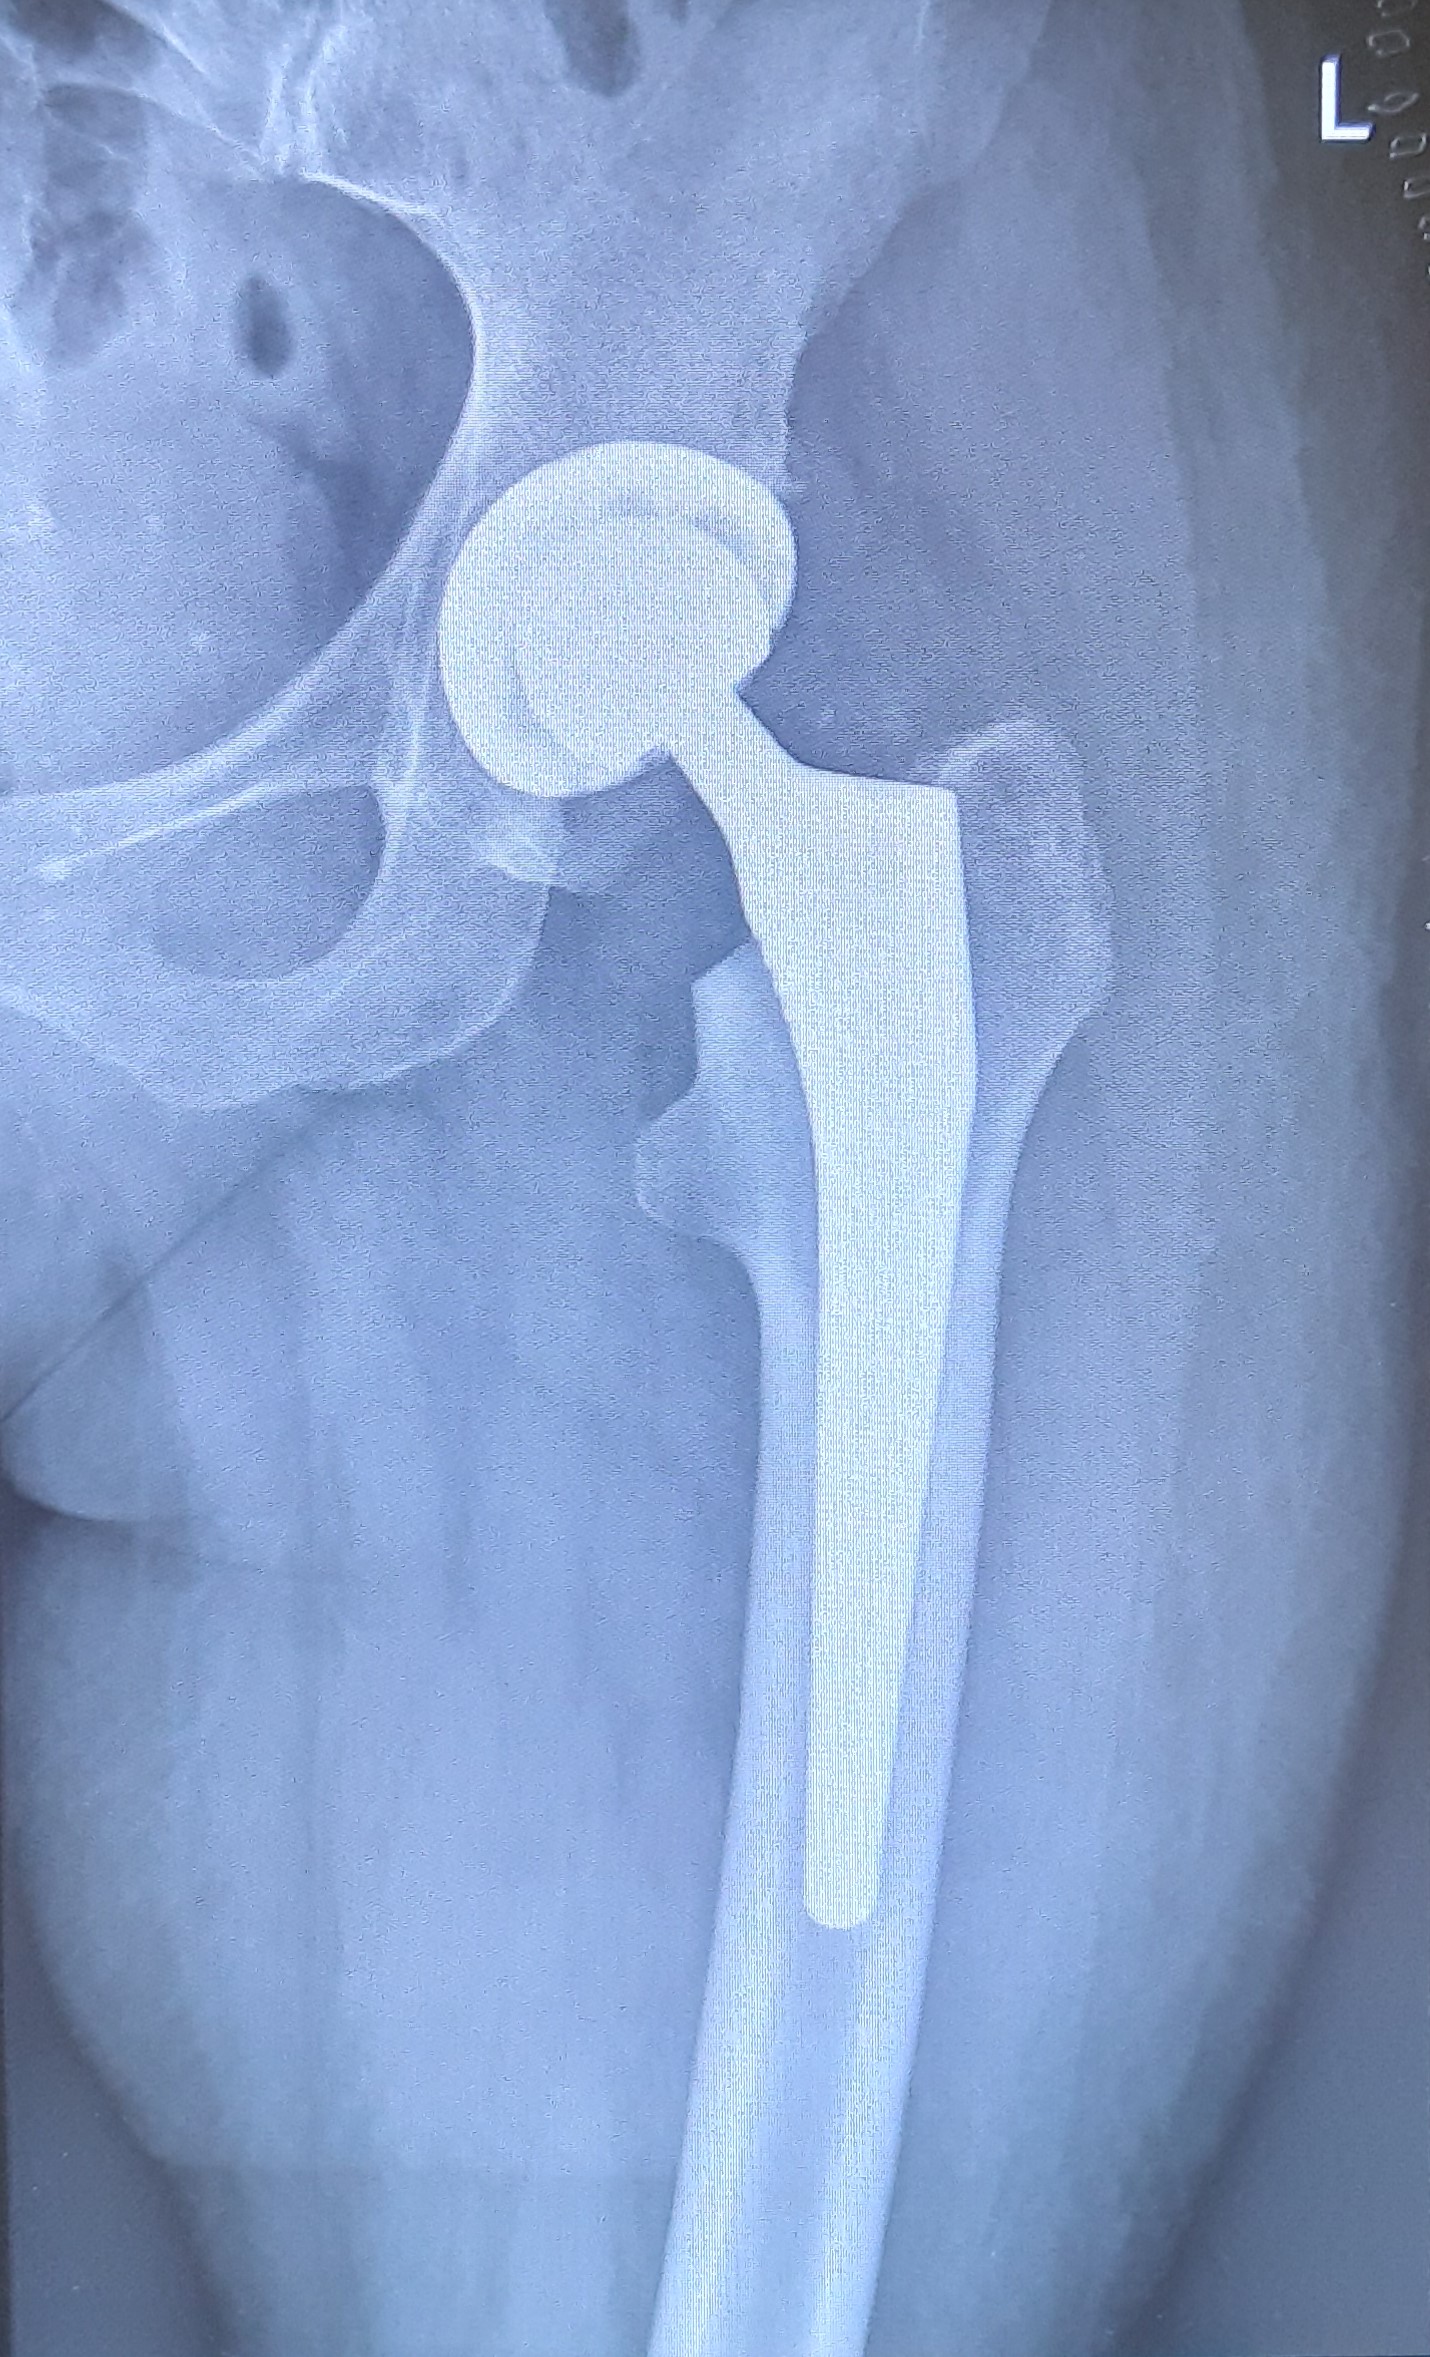

COXARTHROSE - HÜFTPROTHESE

Eine Coxarthrose ist die Arthrose des Hüftgelenkes, also die degenerative Abnützung der artikulierenden Gelenkskomponenten der Hüftpfanne und des Hüftkopfes. Die Häufigkeit der Abnützung nimmt heutzutage aufgrund der steigenden Lebenserwartung und dem höheren Anspruch im Alter stetig zu.

Man kann die primäre (idiopathische) und die sekundäre Coxarthrose unterscheiden, wobei erstere gewöhnlich ohne bekannte Ursache nach dem 60. Lebensjahr beginnt. Die sekundäre Coxarthrose kann ihre Ursache in einer Fehlstellung des Hüftgelenks (Hüftdysplasie), in rheumatischen und bakteriellen Entzündungen sowie als Spätfolge von Traumen haben. Weiters können Übergewicht, Stoffwechselerkrankungen und sportliche Überbelastungen eine Coxarthrose verursachen.

Standardmäßig erfolgt eine Röntgenaufnahme der betroffenen Hüfte in zwei Ebenen sowie eine Beckenübersichtsaufnahme im Stehen. Im Frühstadium sollte zum Ausschluss eines femoroacetabulären Impingement bzw. Labrumpathologien oder einer Hüftkopfnekrose auch eine Magnetresonanztomographie (MRT) in Erwägung gezogen werden.